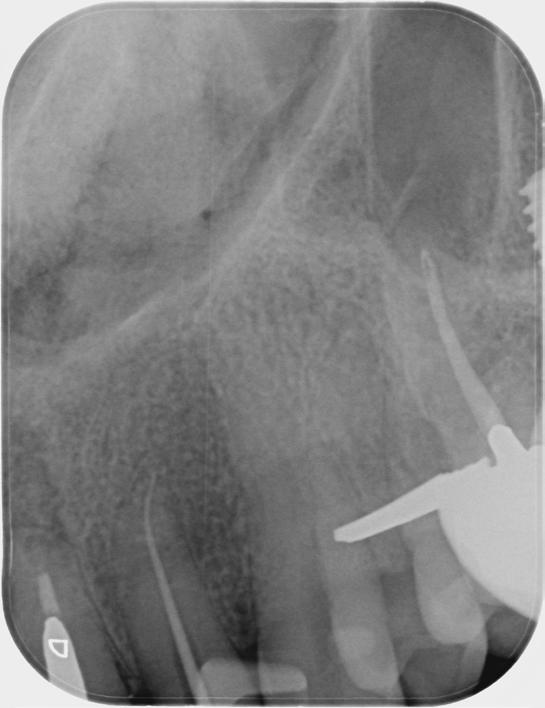

Based on the clinical and radiographic findings, tooth 22 was diagnosed as necrotic with a possibly infected root canal system (RCS), pulp canal calcification and primary acute apical periodontitis due to decay, cracks and restoration breaking down. An endodontic investigation procedure was planned to determine whether the 22 was suitable for further restoration. While the treatment was supposed to be straightforward initially, it progressed to become very complex surprisingly. This was due to separation of a size-10 H-file in the root canal of tooth 22.

The instrument separation was first noticed after taking the initial radiograph to establish the working length. It probably happened due to the patient biting inadvertently on the file during x-ray exposure. As our patient was a bruxer, his bite forced the file deeper in the

severely calcified root canal. The file was now firmly stuck inside the root canal. Despite trying to gently retrieve the file, it broke at junction of the cutting surface to the shank. Bypassing and/or retrieval procedures were planned and performed by using hand files, rotary files and Satelec ultrasonic tips in three different sessions, each one almost three hours long. Rotary files were used mainly as adjunctive instruments.

Taking advantage of rotary files made of a heat-treated alloy with minimal cutting efficiency, designed in a way to scrape rather than cut the dentin, enabled me to safely enlarge the space made by the hand files. This technique also participated in less frequency and chance of breaking more files next to the broken file.

Finally, the broken file segment was removed with braiding barbed broaches around the file. Notably, the patient patiently cooperated all throughout the treatment.

I had a thorough discussion with the patient about the reasons why this incident happened. Even though I could have simply pointed out a severely calcified root canal or a heavy bite to be responsible for the incident, I concluded that the patient’s occlusion should have been assessed carefully during case assessment in order to set preventive measures, which in turn could have potentially saved the patient and I from all the consequences.

Take home message - ALWAYS check your patient’s occlusion during the first examination/ consultation session. It will save you a lot of money!

Fig.1 File got stuck (22/09/2023) Fig.2 File fractured (22/09/2023)

Fig.4 Cut the file deeper (22/09/2023)

Bypassed to WL (12/10/2023)

And even deeper (12/10/2023)

Fig.3 Made space coronally (22/09/2023)

Fig.6 Rotary files used (12/10/2023)

Fig.8 Finally retrieved the file (12/10/2023)